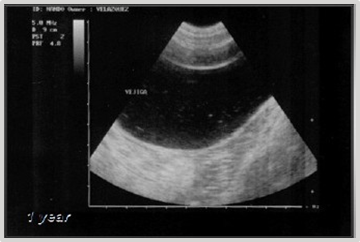

Evolution: The patient's progress occurs without significant clinical signs, except for mild hematuria. Symptomatic and ultrasonographic follow-up at 4, 6 months, and 1 year shows no recurrences (Figures 24) (Figure 25).

Figure 25 Ultrasonographic follow-up at 6 and 12 months post-cryosurgery.

The patient has shown no significant clinical signs except for mild hematuria. Follow-up ultrasonography at 3 months (Figure 36) and 12 months post-cryosurgery showed no recurrence.

Figure 36 Ultrasonographic control at 12 months post-surgery.